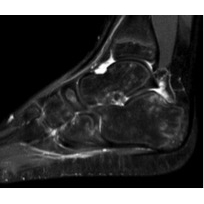

MRI Right Foot: The right foot MRI showed fluid in the anterior aspect of the tibiotalar joint and in the posterior recess of the posterior facet subtalar joint Case Photo #8 . Once again, no bone erosions were seen on MRI of the foot Case Photo #9